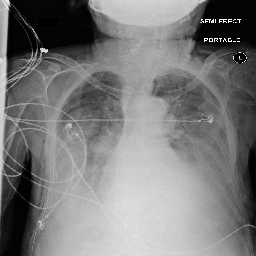

Evaluation of Generated Reports

Ground Truth TieNet Ours (full)

[Uncaptioned image] cardiomegaly is moderate. bibasilar atelectasis is mild. there is no pneumothorax. a lower cervical spinal fusion is partially visualized. healed right rib fractures are incidentally noted. ap portable upright view of the chest. there is no focal consolidation, effusion, or pneumothorax. the cardiomediastinal silhouette is normal. imaged osseous structures are intact. pa and lateral views of the chest. there is mild enlargement of the cardiac silhouette. there is no pleural effusion or pneumothorax. there is no acute osseous abnormalities.

[Uncaptioned image] interval placement of a left basilar pigtail chest tube with improving aeration in the left mid to lower lung and near complete resolution of the pleural effusion. there are residual patchy opacities within the left mid and lower lung as well as at the right base favoring resolving atelectasis. no pneumothorax is appreciated on this semi upright study. heart remains stably enlarged. mediastinal contours are stably widened, although this NAME be related to portable technique and positioning. this can be better evaluated on followup imaging. no pulmonary edema. as compared to the previous radiograph, the patient has been extubated. the nasogastric tube is in unchanged position. the lung volumes remain low. moderate cardiomegaly with minimal fluid overload but no overt pulmonary edema. no larger pleural effusions. no pneumonia. ap upright and lateral views of the chest. there is moderate cardiomegaly. there is no pleural effusion or pneumothorax. there is no acute osseous abnormalities.

Table 4: Sample images along with ground truth and generated reports. Note that upper case tokens are results of anonymization.

Table 4 demonstrates the qualitative results of our full model. In general, our models are able to generate descriptions that align with the logical flow of reports written by radiologists, which start from general information (such as views, previous comparison), positive, then negative findings, with the order of lung, heart, pleura, and others. TieNet also generates report descriptions with such logical flow but in slightly different orders. For the negative findings cases, both our model and TieNet do well on generating reasonable descriptions without significant errors. Regarding the cases with positive findings, TieNet and our full model both cannot identify all radiological findings. Our full model is able to identify the major finding in each demonstrated case. For example, cardiomegaly in the first case, pleural effusion, and atelectasis in the second case.

A formerly practicing clinician co-author reviewed a larger subset of our generated reports manually. They drew several conclusions. First, our full model tends to generate sentences related to pleural effusion, atelectasis, and cardiomegaly correctly—which is aligned with the clinical finding scores in Table 3. TieNet instead misses some positive findings in such cases. Second, there are significant issues in all generated reports, regardless of the source model, which include the description of supportive lines and tubes, as well as lung lesions. For example, TieNet is prone to generate nasogastric tube mentions while our model tends to mention tracheostomy or endotracheal tube, and yet both models have difficulty identifying some specific lines such as chest tube or PICC line. Similarly, both systems do not generate the sentence with positive lung parenchymal findings correctly.

From this (small) sample, we are unable to draw a conclusion whether our model or TieNet truly outperforms the other since both present with significant issues and each has strengths the other lacks. Critically, neither of them can describe the majority of the findings in the chest radiograph well, especially for positive cases, even if the quantitative metrics demonstrate the reasonable performance of the models. This illustrates that significant progress is still needed in this domain, perhaps building on the directions we explore here before these techniques could be deployed in a clinical environment.